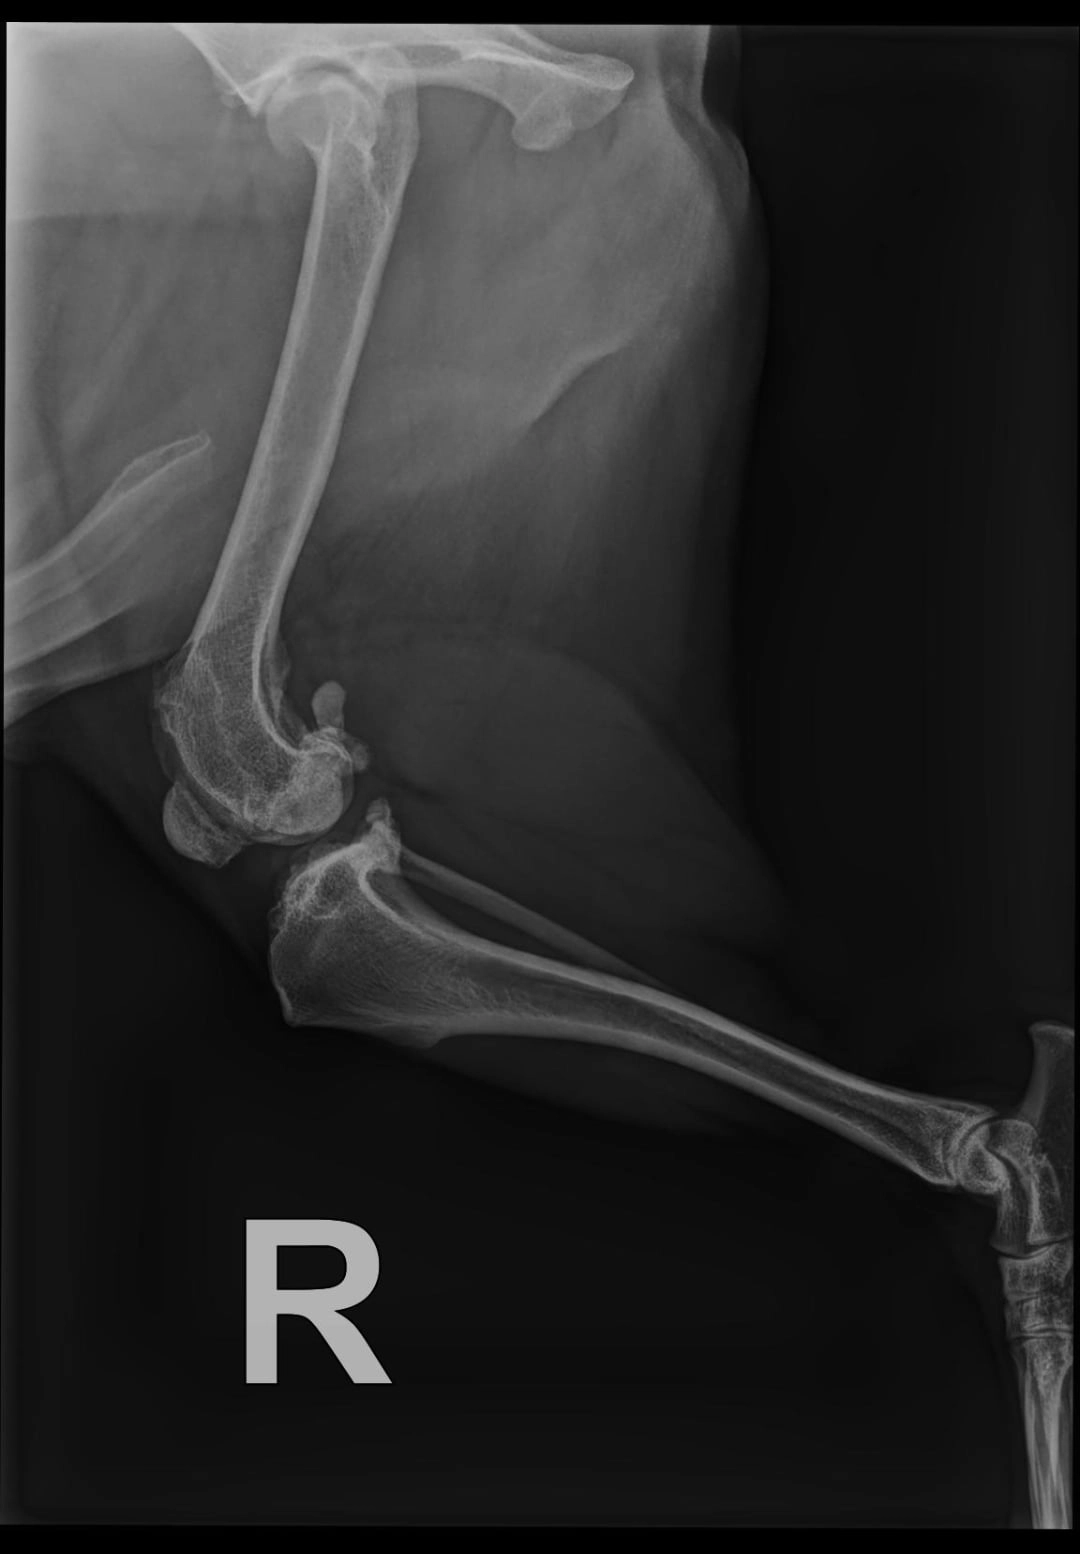

Niedawno zdiagnozowano u niego poważne problemy ortopedyczne. Badanie RTG wykazało:

- silne zmiany zwyrodnieniowe i przebudowę główki kości udowej w lewym stawie biodrowym,

- zmiany zapalne w prawym stawie kolanowym (podejrzenie tzw. myszy stawowej).

W pierwszej kolejności konieczna jest operacja lewego biodra - dekapitacja główki kości udowej.